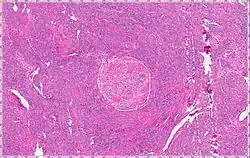

| Intravenous Leiomyoma |

Intravenous leiomyomatosis is a rare condition seen exclusively in women in which leiomyomata, benign smooth muscle tumors, are found in veins. The masses are benign-appearing but can spread throughout the venous system leaving the uterus and even cause death when growing into the heart from the IVC.[1] While the possibility that these arose de novo from the smooth muscle in the blood vessel wall was considered, chromosomal analysis suggests a uterine origin.[2] Intravenous leiomyomata are usually but not always associated with uterine fibroids, and tend to recur.